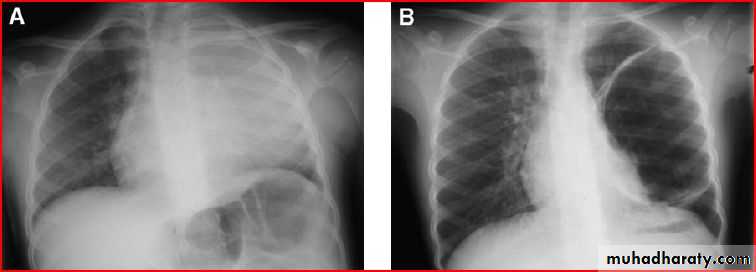

Homgenous opacity filling the rt. Hemithorax there is shefting in trachea to rt. Side mean this is collapse

Opacification of whole lt. hemithorax consolidation of pneumonea but no pleural effusion b.c there is free costophrenic angle